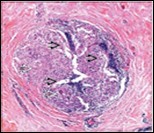

Figure 4.Granulomatous mastitis with epitheloid cell granuloma, langhans and foreign body giant cells with lymphocytic rimming12.

Granulomatous  mastitis with                epitheloid cell granuloma, langhans and              foreign body giant cells with lymphocytic              rimming12.

Core needle biopsy of idiopathic granulomatous mastitis enunciates multiple aggregates of non- caseating epitheloid cell granulomas within and encompassing breast lobules, constituted of epitheloid histiocytes, lymphocytes, neutrophils and multinucleated giant cells. Granulomatous inflammation is predominantly lobulo-centric. The inflammation is preponderantly composed of lymphocytes, plasma cells, epitheloid histiocytes, multinucleated giant cells and neutrophils. Neutrophils can configure micro-abscesses and encompass vacant micro-cystic cavities, morphological features which are in common with cystic neutrophilic granulomatous mastitis. Non specific lobulitis along with a lymphoid and plasma cell infiltrate accompanies the granulomatous inflammation. Necrosis is usually absent. Neutrophilic micro-abscesses can be accompanied by fistula formation 4, 5.

Multinucleated giant cells are detected in an estimated three fourths (78.5%) instances. Plasma cells are discernible in around half (53.9%) of the subjects and usually appear at the margins of cystic vacuoles with centric accumulation of neutrophils within the granulomas.

Despite a varied differential diagnosis, granulomatous mastitis is predominantly an idiopathic disorder2, 3. Possible association of Corynebacterium infection with granulomatous mastitis can be observed and is designated as cystic neutrophilic granulomatous mastitis. Aforesaid condition typically displays lipo- granulomas comprised of clear, vacuolated spaces with a peripheral rimming of neutrophils along with a circumscription of granulomatous inflammation 2, 3.

A distinctive histological attribute of granulomatous inflammation admixed with acute inflammation and concurrent cystic spaces indicates a probable accumulation with exceptional, gram positive bacilli within the clear, vacuolated spaces. Microbiological analysis for isolation of Corynebacterium, particularly Corynebacterium kroppenstedtii is necessitated in concurrence with aforesaid morphological aspects to arrive at a cogent diagnosis. Corynebacterium is a gram positive bacillus which appears as a constituent of skin microbiota. Thus, a possible source can be on account of bacterial colonization, infection or contamination. Corynebacterium kroppenstedtii can be isolated in around two fifths (40%) instances of definitive granulomatous lobar mastitis 6, 7.